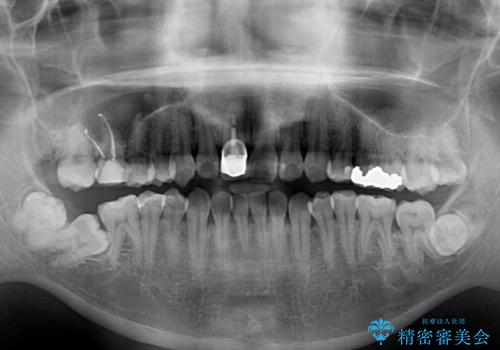

- 前歯のデコボコと上下のクロスバイトを気にして来院された患者様です。

インビザラインを用い、IPR(歯と歯の間を削る)と歯列全体を拡大させることで、歯並びを整えていくこととしました。

上の前歯が下の前歯を乗り越える際、奥歯がほとんど咬めない時期があり、乗り越えた後も、インビザライン特有の奥歯の咬みにくさが続きました。

咬み合わせ改善のために治療期間を要しましたが、最終的に奥歯はしっかりと咬めるようになりました